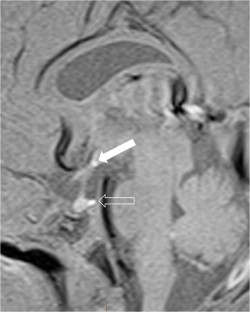

We selected pediatric head MRI examinations from 2005 to 2017 based on the finding of a double midline sellar and suprasellar bright spot on T1-weighted sequence. Medical history, physical examination, pituitary hormonal profile and bone age evaluation were extracted from the medical record of the selected patients. An experienced pediatric neuroradiologist reviewed head MRIs, which were performed on 3-tesla (T) magnet and included at least sagittal T1-weighted imaging centered on the sella turcica obtained with and without fat suppression.

In six cases, two midline bright spots were identified on T1-weighted sequences obtained both with and without fat suppression. While one spot was located at the expected site of the neurohypophysis in the posterior sella, the second one was in the region of the median eminence, suggesting partial ectopic posterior pituitary gland. Growth hormone deficiency, either isolated (n=1) or combined with thyroid stimulating hormone deficiency (n=1) was found. None of the children had clinical signs of posterior pituitary dysfunction.

Fig. 1